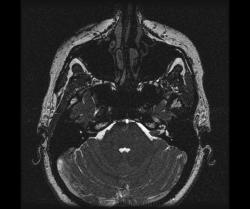

Пациентка, 33 года. Обратилась к ЛОР-врачу с жалобами на прогрессирующую левостороннюю тугоухость, эпизоды вертиго. Было рекомендовано проведение МРТ.

На стандартных аксиальных срезах сразу привлек внимание расширенный вестибулокохлеарный нерв слева:

МРТ с контрастированием гадодиамидом. Видна небольшая внутриканальцевая невринома правого слухового нерва (указана стрелкой).

Невриномы в этой стадии обычно не вызывают сдавления или смещения ствола либо их влияние на мост мозга, продолговатый мозг и мозжечок минимально. Гипертензионные и стволовые симптомы отсутствуют или выражены слабо. Наиболее частыми локальными симптомами являются поражения ЧН в мостомозжечковом углу с наиболее частым ранним вовлечением слухового нерва. В связи с этим у пациентов с односторонним снижением слуха следует подозревать невриному VIII нерва до тех пор, пока она не будет исключена. Все больные с односторонним нарушением слуха должны наблюдаться в динамике у отоневролога